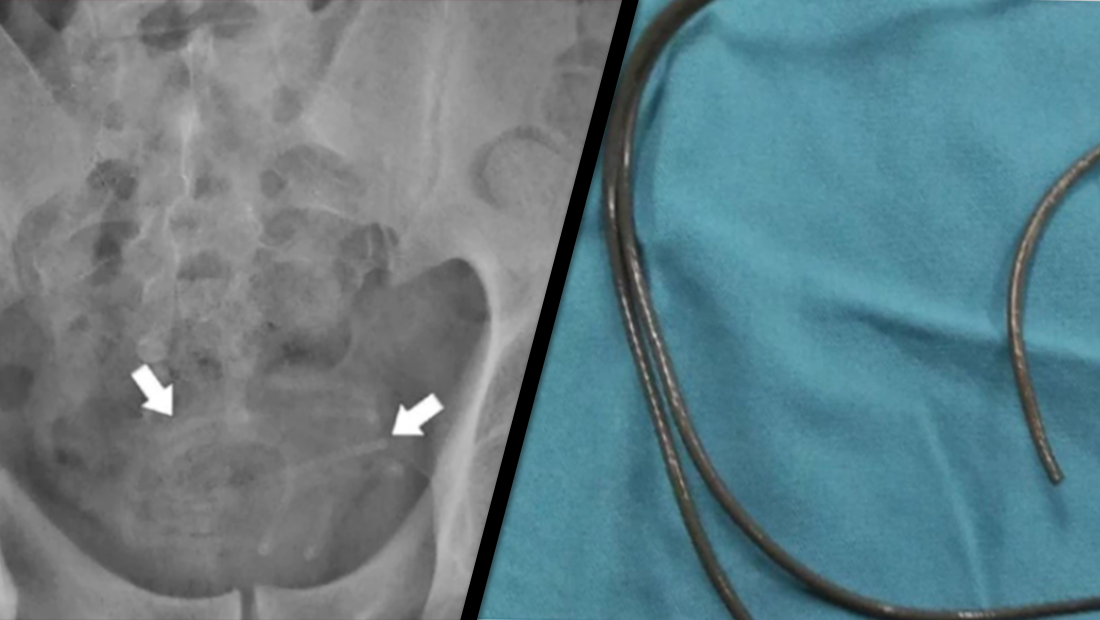

A 34-year-old bloke from Indonesia got carried away having some 'alone time' recently, and shoved an 80cm-long-earphone wire down his urethra.

The wire got lodged in the man's bladder and he began experiencing agonosing pain while peeing, The Sun reports.

The doctors quickly found and removed the wire, which thankfully hadn't attatched to the bladder wall.